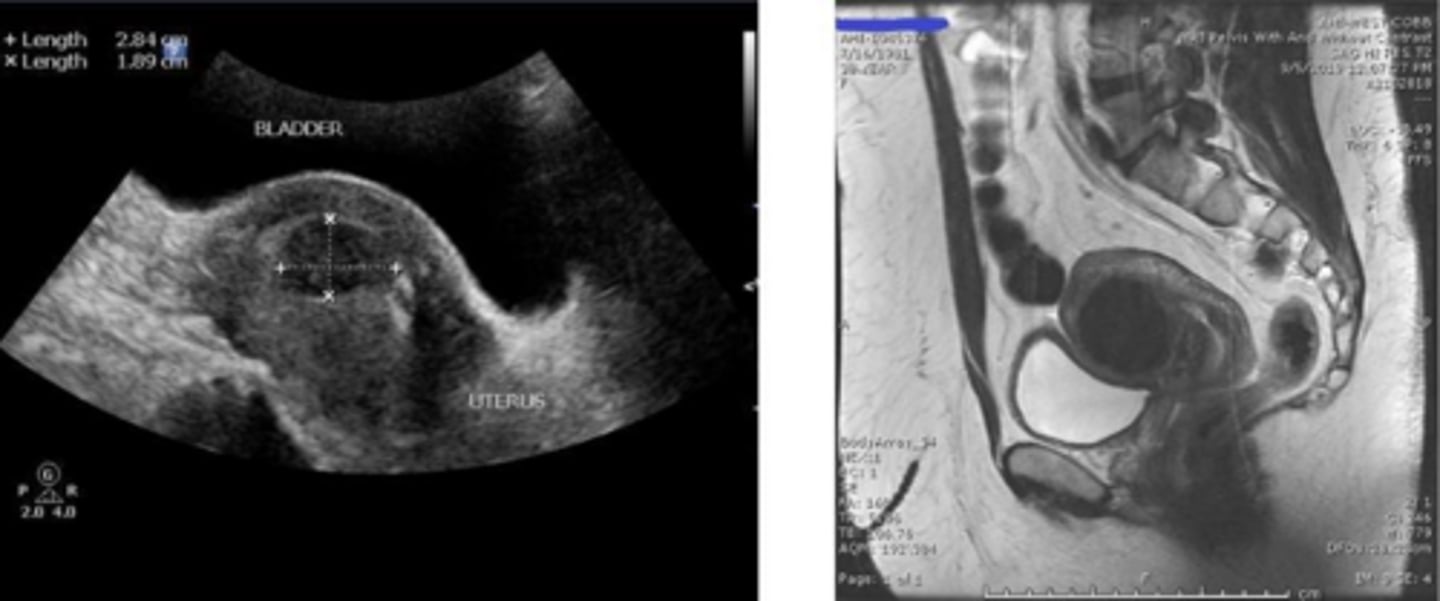

What is the first-line and gold-standard imaging modality for diagnosing uterine fibroids?

Pelvic ultrasound (transvaginal and transabdominal).

When is Saline Infusion Sonohysterography (SIS) indicated for the evaluation of uterine fibroids?

Best for visualizing submucosal fibroids and cavity distortion.

When is MRI typically indicated for the evaluation of uterine fibroids?

It is reserved for surgical planning (e.g., myomectomy) or when malignancy is suspected.

What is the characteristic ultrasound appearance of a complete mole?

A 'snowstorm' or 'grapes' appearance due to hydropic villi, with no fetal tissue.

What is the characteristic ultrasound appearance of a partial mole?

A 'Swiss cheese' placenta with fetal tissue present.